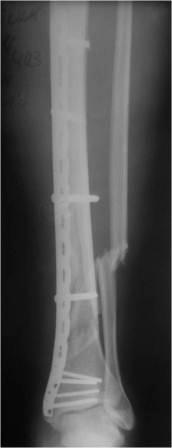

Здравствуйте, Уважаемые коллеги. Поступил пациент, травма в результате ДТП в качестве

пассажира. Получил закрытый винтообразный перелом обеих костей левой голени в нижней трети

со смещением отломков.При поступлении скелетное вытяжение за пяточную кость 5 кг груз.

Через неделю малоинвазивный остеосинтез большеберцовой кости премоделированной

пластиной и винтами. При попытке самостоятельной активизации на костылях упал на

оперированную конечность. Повторные снимки -угловая деформация. Наложена задняя

гипсовая лонгета, отпущен на 2 недели до заживления послеоперационных ран. Планируем

реостеосинтез. Мыслей много. Хотелось бы узнать и Ваше мнение. Спасибо. (Rg снимки

прилагаются)